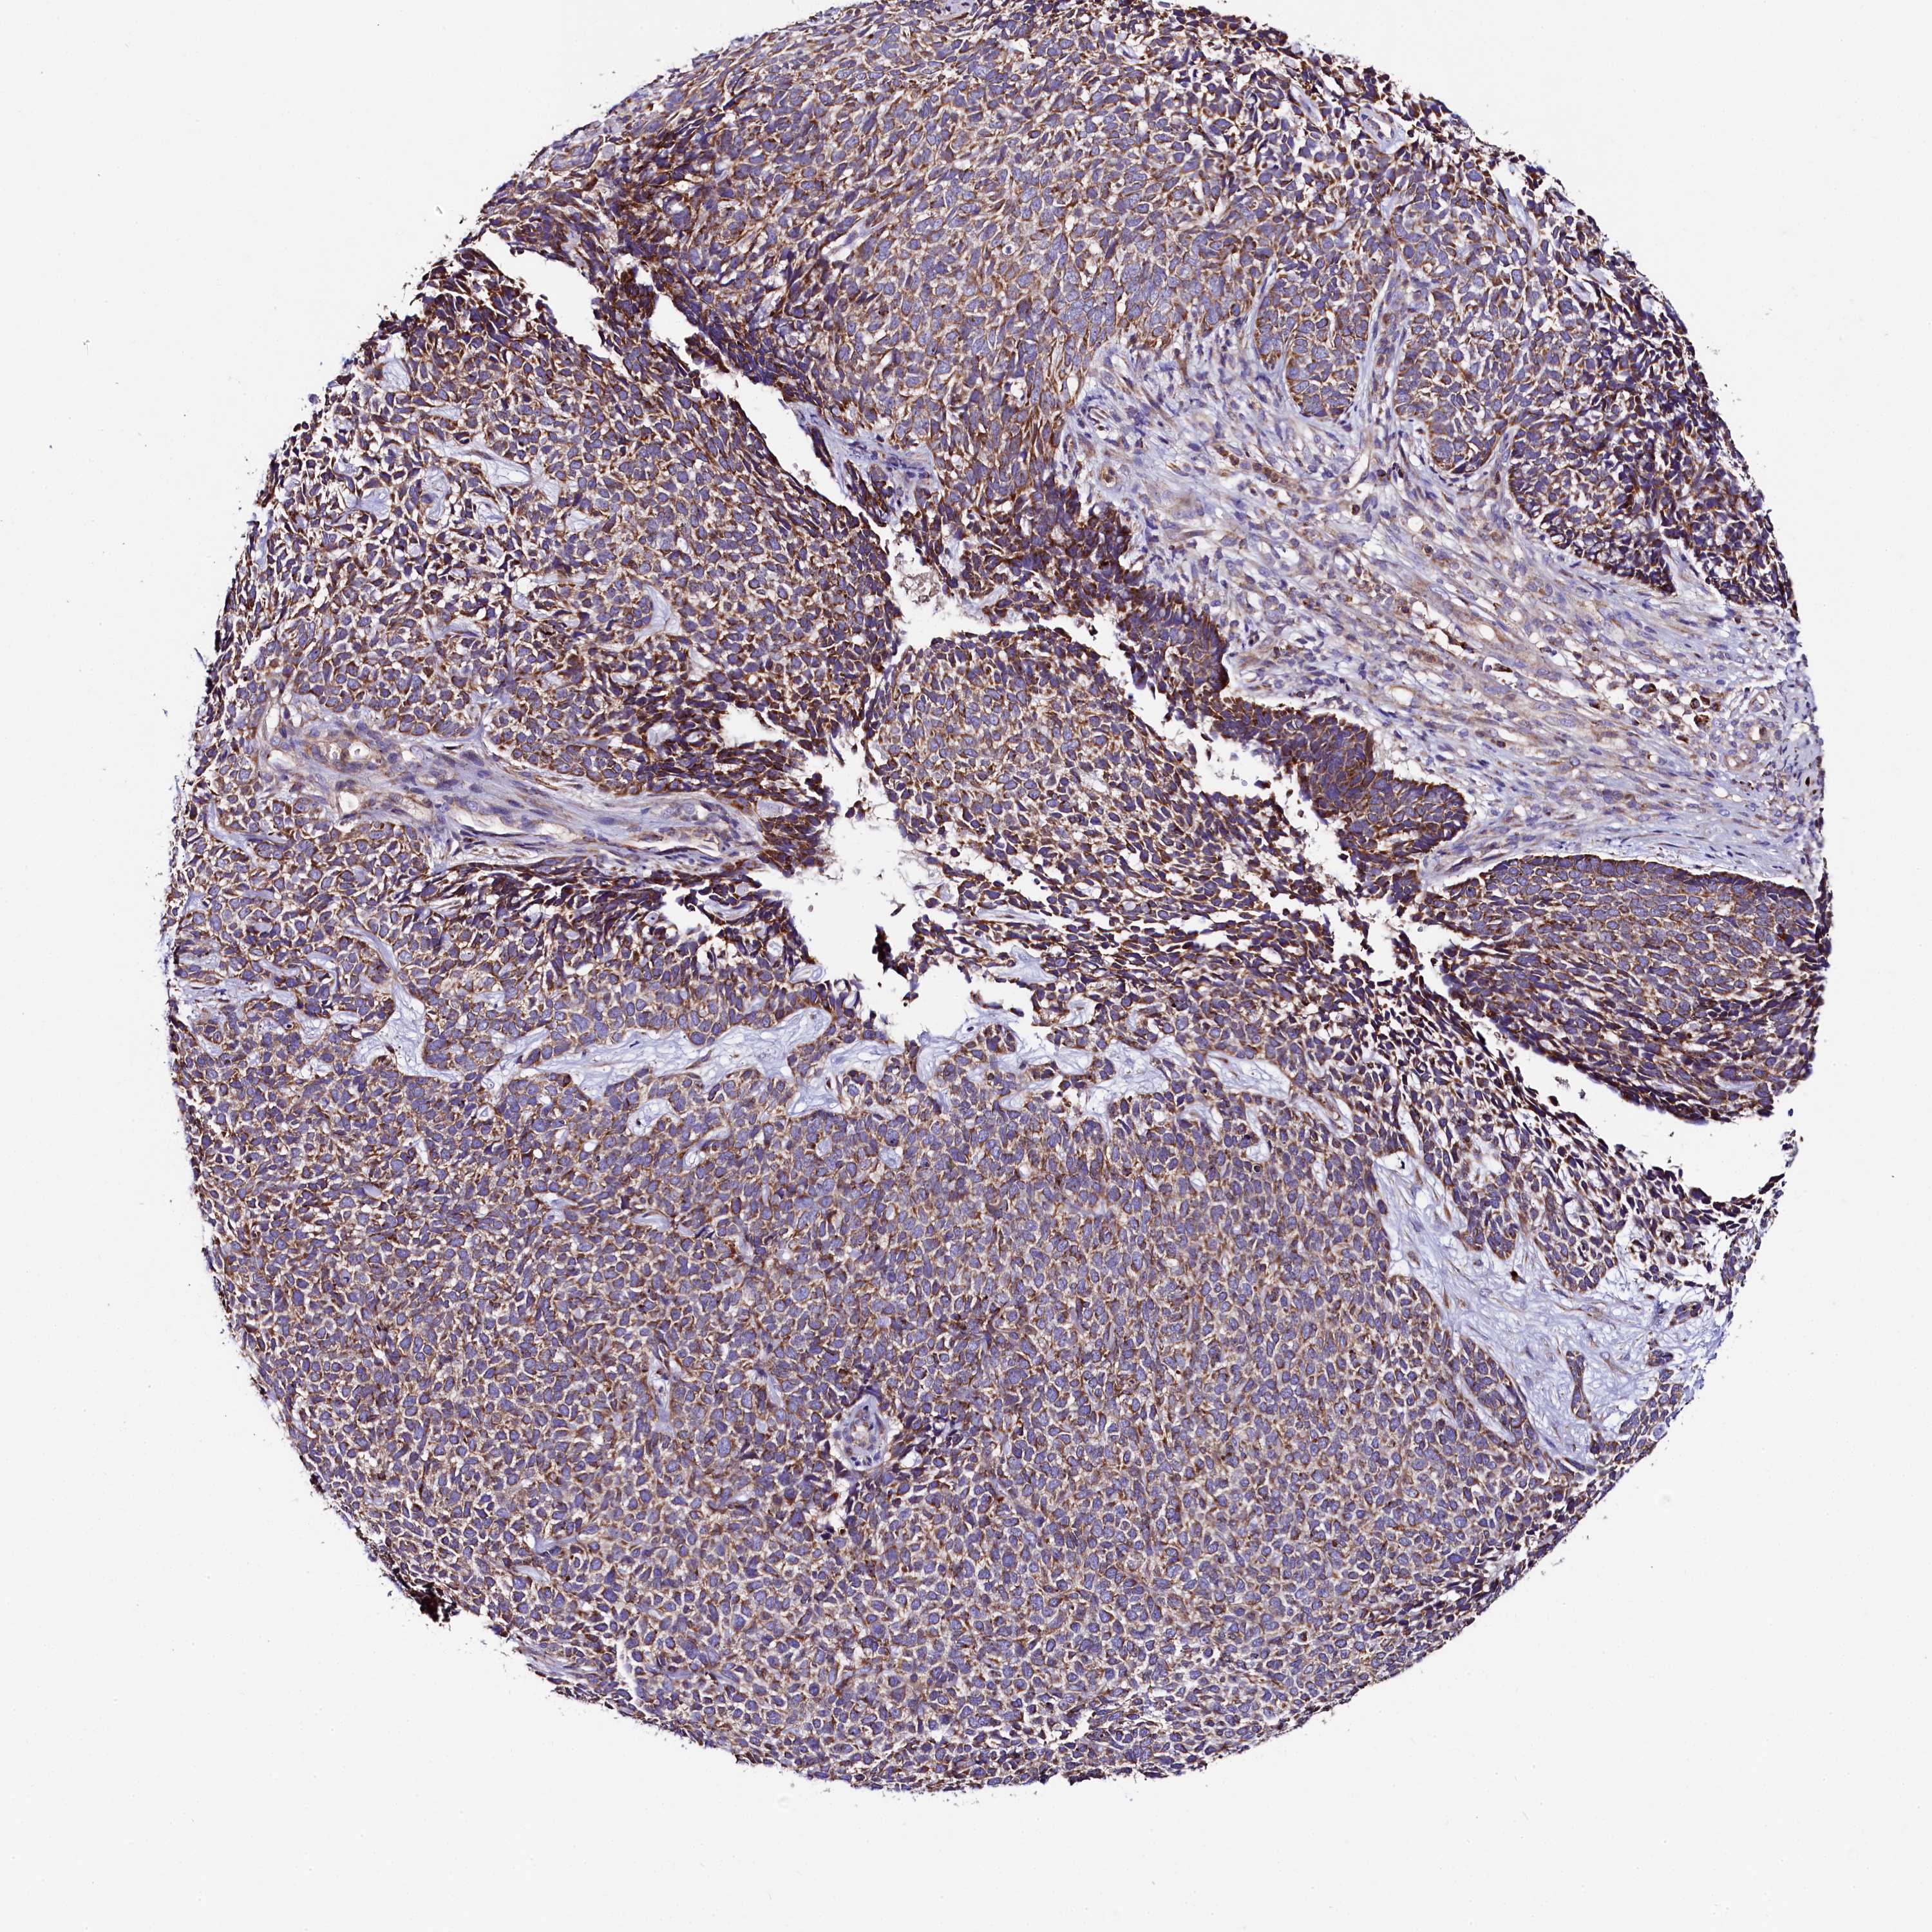

CANCER SKIN CANCER Show tissue menu

Basal cell and squamous cell cancer

SKIN CANCER - Protein expressioni

A mouse-over function shows sample information and annotation data. Click on an image to view it in a full screen mode. Samples can be filtered based on level of antibody staining by selecting one or several of the following categories: high, medium, low and not detected. The assay and annotation is described here.

Each image is clickable and will lead to virtual microscopy that enables deeper exploration of all samples and also displays staining intensity scores, fraction scores and subcellular localization as well as patient and tissue information for each sample.

Antibody HPA039959

Basal cell carcinoma